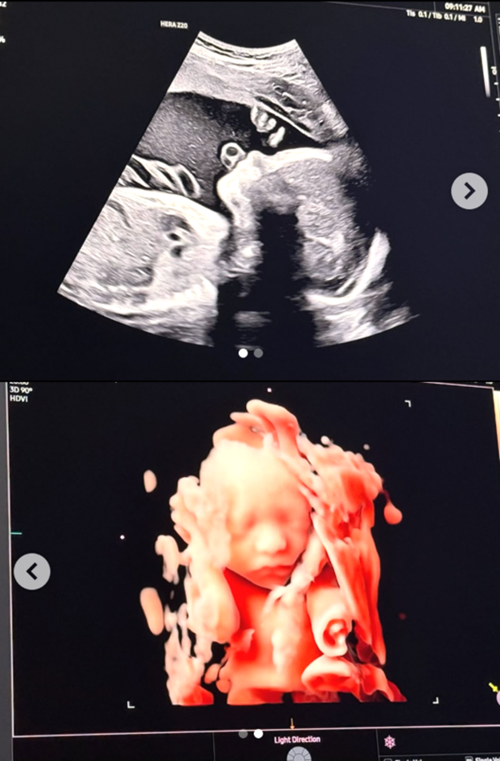

4月21日、ソン・スンヒョンは自身のSNSで「もうすぐ会おう、僕たちのヘニミ(太陽)」というコメントとともに、複数の写真を公開した。

公開された写真には、生まれてくる子どものエコー写真が収められている。特に3Dエコー写真には、ソン・スンヒョンにそっくりな顔立ちが映っており、注目を集めている。